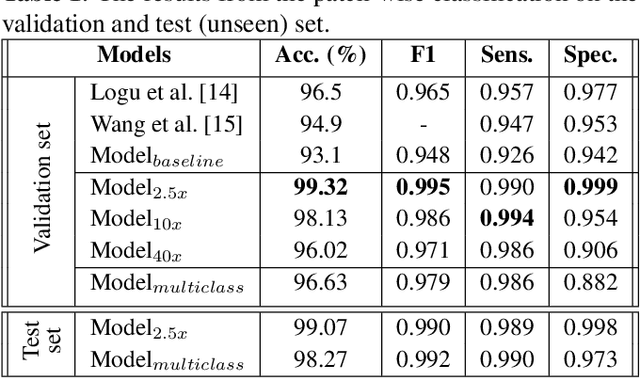

Melanoma diagnosed and treated in its early stages can increase the survival rate. A projected increase in skin cancer incidents and a dearth of dermatopathologists have emphasized the need for computational pathology (CPATH) systems. CPATH systems with deep learning (DL) models have the potential to identify the presence of melanoma by exploiting underlying morphological and cellular features. This paper proposes a DL method to detect melanoma and distinguish between normal skin and benign/malignant melanocytic lesions in Whole Slide Images (WSI). Our method detects lesions with high accuracy and localizes them on a WSI to identify potential regions of interest for pathologists. Interestingly, our DL method relies on using a single CNN network to create localization maps first and use them to perform slide-level predictions to determine patients who have melanoma. Our best model provides favorable patch-wise classification results with a 0.992 F1 score and 0.99 sensitivity on unseen data.